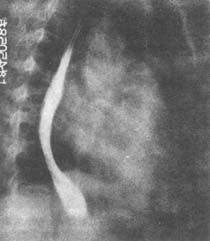

X線檢查示肺動脈乾突出,左心房大,右心室大,左主支氣管上抬,食道可見左房壓跡。肺上部血管影增多、增粗,肋隔角可見Kerley'sB線。ECG示:P波增寬>0.11s,有切跡,右心室肥大;後期可有房顫。UCG示二尖瓣瓣膜增厚、粘連、鈣化,瓣口狹窄,左房、右心室腔擴大,心房可見血栓;都卜勒超聲示二尖瓣下舒張期湍流頻譜。